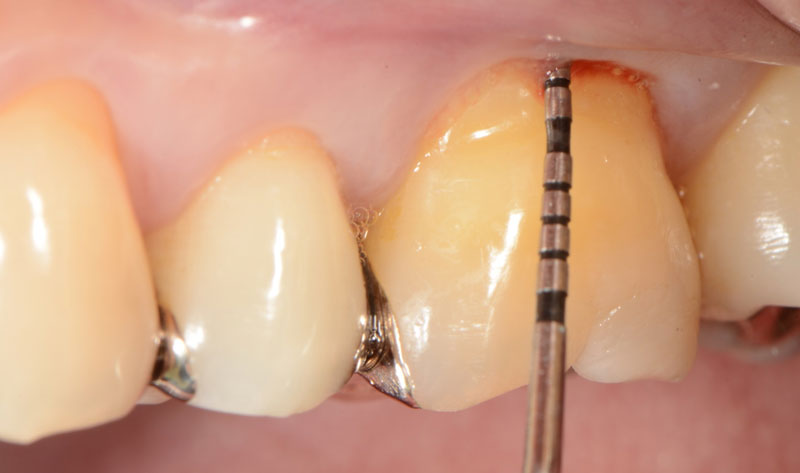

症例②

歯肉の腫脹を主訴に来院されました。歯周ポケットは深く、骨欠損が認められます。

肉芽組織除去後の頬側です。